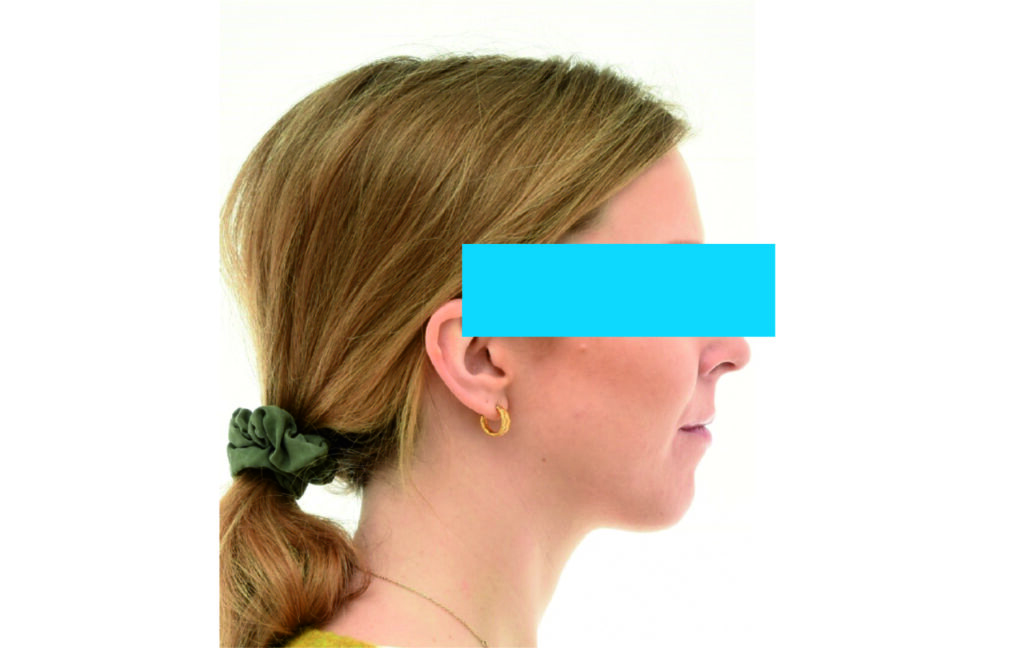

Patient introduction

Age: 25

Gender: Female

Angle Class II 2mm on the right, Angle Class II 2mm on the left, light mandibular asymmetry to the right, lower central line 1mm to the right, upper central line 1,5mm to the left, 1mm overjet and overbite. Sagittal asymmetry of upper dental arch. Light crowding upper and lower frontal segments, severe attrition of posterior teeth, night bruxism. Normal sagittal position of both jaws, high angle case, steep mandibular ramus,excessive lower facial height, open bite tendency.

Soft Tissue Analysis: convex profile, lower third of the face increased, slightly retrusive upper and lower lips, lip strain on closure.